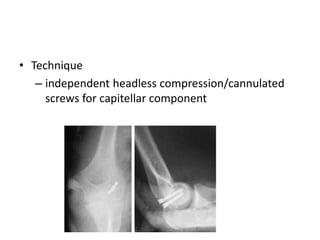

CAPITELLAR #

ORIF with posterior approach with or without

olecranon osteotomy

• Indications

– capitellar fractures with associated

fractures/injuries to distal humuers/olecranon

and/or medial side of the elbow

• Approach

– indicated when more extensive articular work is

needed

– lateral decubitus positioning

• Technique

– independent headless compression/cannulated

screws for capitellar component